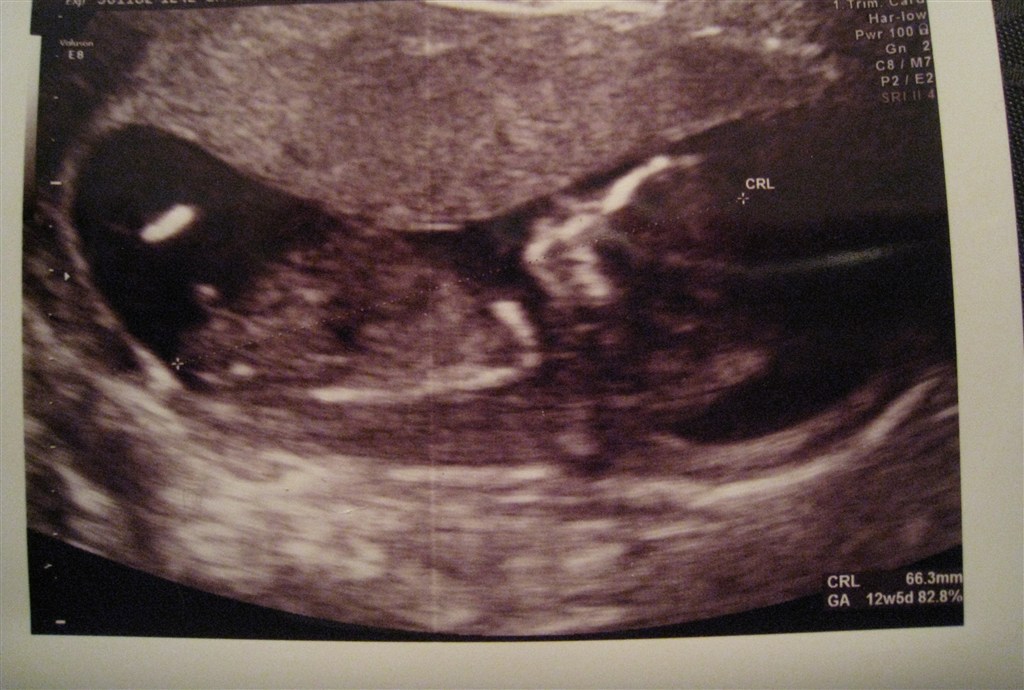

Ja sikke en nærmest uvirkelig forandring der er sket fra vores tidlig scanning i uge 8 og så frem til nu i uge 13.. Efter idag, må jeg simpelthen bare begynde at tro på det, sådan rigtig og for alvor..

Vi fik endda vist rigtig fine til risiko vurderingen - 14.398.. Weee!!!